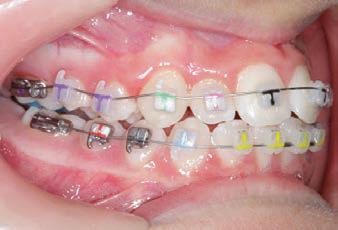

PROGRESS 3 - 30/10/18 - With M-TWO .020 x .020 Cu Nitanium 35° archwire

PROGRESS 4 - 27/11/18 - 3 links power chain: 5, 4, bypass 3 to crimp hooks

PROGRESS 5 - 13/3/19 - With M-TWO .020 x .020 Cu Nitanium 35° archwire

PROGRESS 6 - 1/8/19 - With M-THREE.019 x .025 Beta Titanium wire